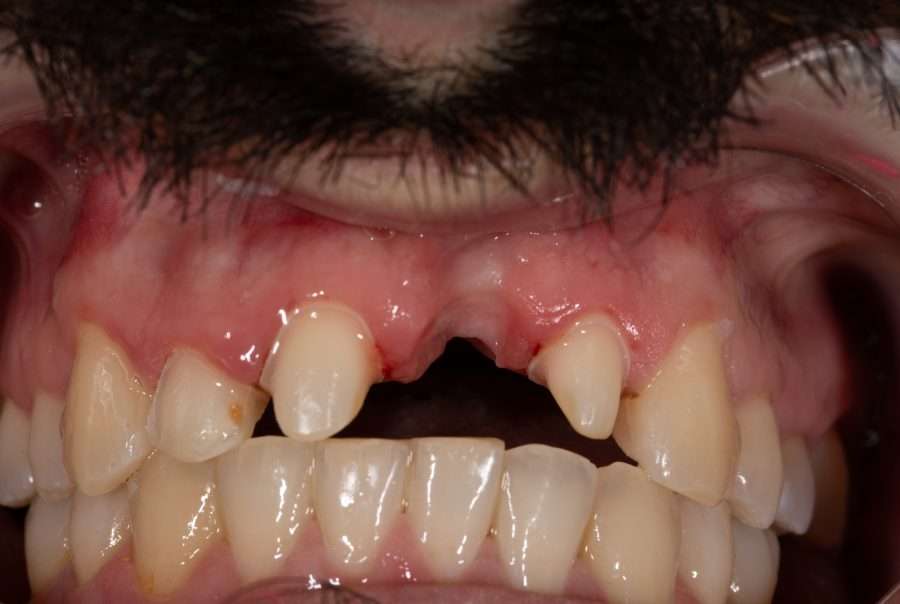

Lost central incisor

We chose an exclusively prosthetic approach in this case of replacing a previously lost central incisor, with a history of trauma, multiple endodontic retreatments, significant mobility and substantial bone tissue loss.